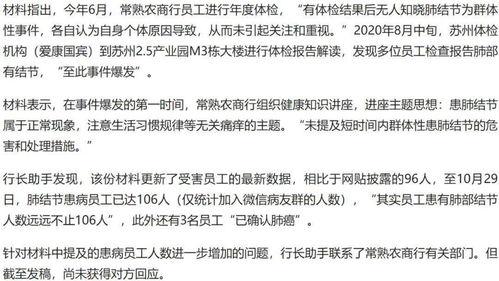

话说那天,一位自称是科兴生物员工的网友,在社交媒体上发布了一段视频。视频中,这位员工声称自己患有肺结节,并指责公司工作环境存在严重问题。视频一经发布,立刻引起了广泛关注,网友们纷纷转发讨论,质疑声此起彼伏。

面对网友的质疑,科兴生物迅速作出回应,表示将对此事进行调查。同时,相关部门也介入调查,力求还原真相。

经过调查,发现这位员工的肺结节确实存在,但并非由工作环境导致。专家表示,肺结节的形成与多种因素有关,包括遗传、生活习惯等。虽然工作环境可能对肺结节的形成有一定影响,但并非唯一原因。

尽管调查结果显示肺结节并非由工作环境导致,但这位员工的遭遇仍然引起了广泛关注。许多网友纷纷表示同情,并质疑科兴生物的工作环境是否真的存在问题。

据了解,这位员工在科兴生物工作多年,一直从事研发工作。他表示,公司工作环境较为封闭,员工长时间处于高压力状态。此外,公司对员工的健康关注不足,导致一些员工在不知情的情况下患上疾病。